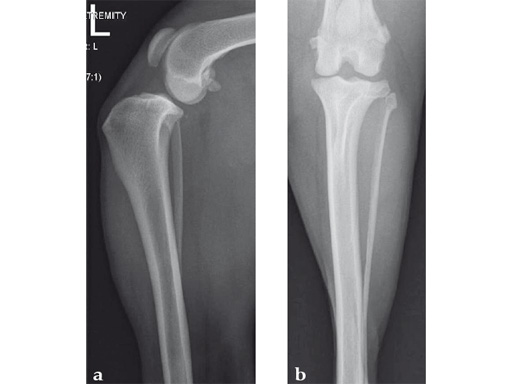

A 10-year-old female, spayed, 6.0 kg cat had a partial tear of the left cranial cruciate ligament, meniscal mineralization, and a medial meniscal tear. The cat was treated with a partial meniscectomy and TPLO . A 2.0 mm TPLO plate was perfect for this cat due to the slope of the tibial plateau (25) and the size of the cat. Three 2.0 mm locking screws were used proximally and three 2.0 mm cortex screws were used distally. The contour of this plate does not perfectly match the contour of the proximal tibia, but use of locking screws in this segment avoids any potential angulation of the segments as the screws are tightened. The cat healed uneventfully and returned to normal function.